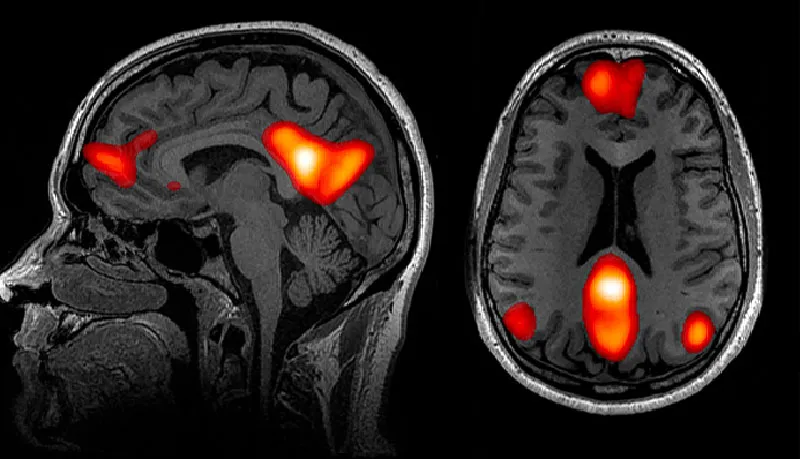

Японы эрдэмтдийн баг 65-аас дээш насны 9,000 орчим хүнийг хамруулсан томоохон судалгаанд оролцогчдын тархины дүрс бичлэгийг шинжилжээ. Нийгмийн харилцаа багатай хүмүүсийн тархины эзэлхүүн мэдэгдэхүйц бага, ялангуяа ой санамж, сэтгэл хөдлөлийг хариуцдаг гиппокамп ба амигдала хэсэгт агшилт илэрснийг тогтоосон байна. Мөн цусны эргэлтийн тогтолцооны гажиг, танин мэдэхүйн чадамж буурах зэрэгт нөлөөлдөг цагаан бодисын гэмтэл (white matter lesion) ихээр ажиглагджээ.

Энэхүү судалгаа 2023 оны 7 дугаар сарын 12-нд Neurology сэтгүүлд “Association of Social Isolation With Brain Atrophy and White Matter Lesions in Older Adults” нэртэйгээр нийтлэгдсэн бөгөөд нийгмийн оролцоо ба тархины эрүүл мэндийн уялдааг анхааруулсан хамгийн том судалгааны нэгт тооцогдож байна.